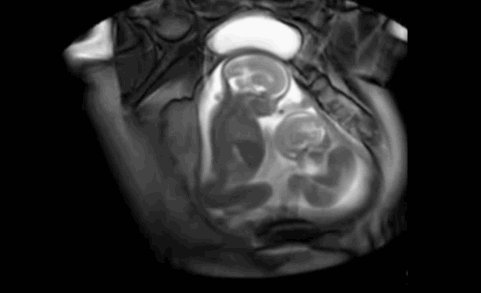

擁有雙胞胎寶寶父母當然都很幸福,雖然養育兒女付出了雙份的辛苦,但同時也收穫了雙份的歡樂。  他們在媽媽肚子的時候就已經頻頻互動,有時候還會親吻,打架!超級萌,超級感人!

雙胞胎居然在打架   其實雙胞胎是心有靈犀的,看下面的這兩對雙胞胎,你就知道有多羨慕了 1、當這對雙胞胎從媽媽肚子裡生出來的那一刻,竟讓醫院所有人都震驚了!!原來這對雙胞胎竟是.手拉手出生的! 而當寶寶生下來的一刻,大家都驚呆了  爸爸都感動的哭啦 2、雙胞胎中的弟弟出生就沒呼吸,哥哥給他加油打氣,居然拉起弟弟的手 出生時,弟弟被查出了胸部感染,需要靜脈注射抗生素,這時哥哥竟然把手伸過來緊緊握住了弟弟的手。 「不要怕,哥哥保護你。」  就在護士向媽媽解釋如何治療的時候,突然哥哥伸出手去摸瓊斯,弟弟感覺到了就伸手來回應,然後他倆的手緊緊的握在了一起。這一幕太令人難以置信了!